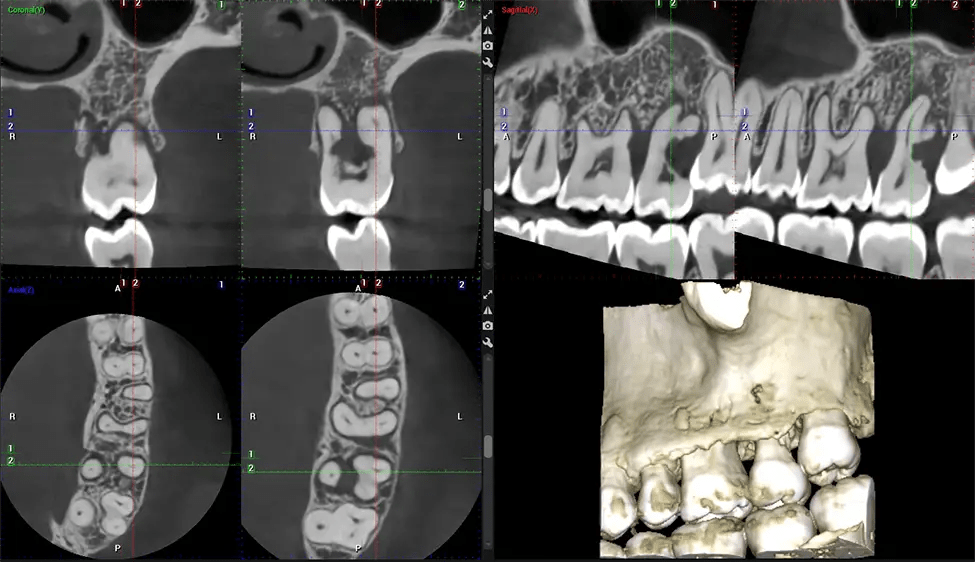

Esta exploración 3D, llamada tomografía computarizada de haz cónico, le brinda a su dentista una imagen más completa de su anatomía bucal y sus procesos patológicos que una radiografía tradicional. A diferencia de las radiografías convencionales, que capturan una imagen 2D de la boca desde varios ángulos, una exploración 3D toma varias radiografías digitales para una imagen. Proporciona una vista completa de la mandíbula, los dientes, los nervios y los tejidos blandos. Esta vista mejorada permite a los dentistas detectar problemas menores que no son visibles en las exploraciones 2D tradicionales, como muelas del juicio impactadas o fracturas óseas en la cavidad sinusal.

Otro beneficio importante es que las imágenes 3D proporcionan imágenes más precisas de la estructura ósea. Estas imágenes son más detalladas y le brindan un diagnóstico más preciso. Un diagnóstico preciso significa un mejor tratamiento para usted.

Cuando se combina con extracciones, colocación de implantes dentales o injertos óseos, la tecnología CBCT puede brindarle una experiencia más rápida y mucho más cómoda. Esto se debe a que la imagen 3D proporciona una imagen más detallada de toda su cavidad bucal, lo que le permite a su dentista guiarlo en cada paso del proceso antes de que ocurra. Esto a menudo ayuda a los pacientes a sentirse más preparados y cómodos en general, especialmente si han tenido una experiencia traumática con tratamientos dentales anteriores.